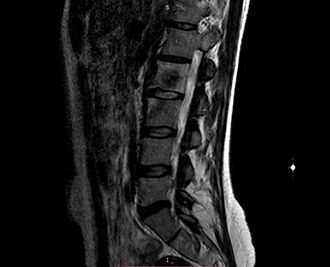

Рентген позвоночника

Позвоночник является несущим элементом скелета человека, а потому — и наиважнейшим. Он подвержен целому ряду заболеваний, ранее выявление которых позволяет избежать серьёзных осложнений, негативно влияющих на качество жизни человека. Важную роль в процессе диагностирования играет рентген позвоночника. Это — высокоинформативная диагностическая методика, которую ещё называют «спондилография». Она позволяет врачам получить данные о том, в каком состоянии пребывает позвоночник пациента, о перенесённых травмах и их последствиях. Благодаря ей, также, можно оценить состояние спинномозгового канала и выявить практически все его патологии.

Рентгенография шейного отдела позвоночника в клинике ЦЭЛТ в Москве